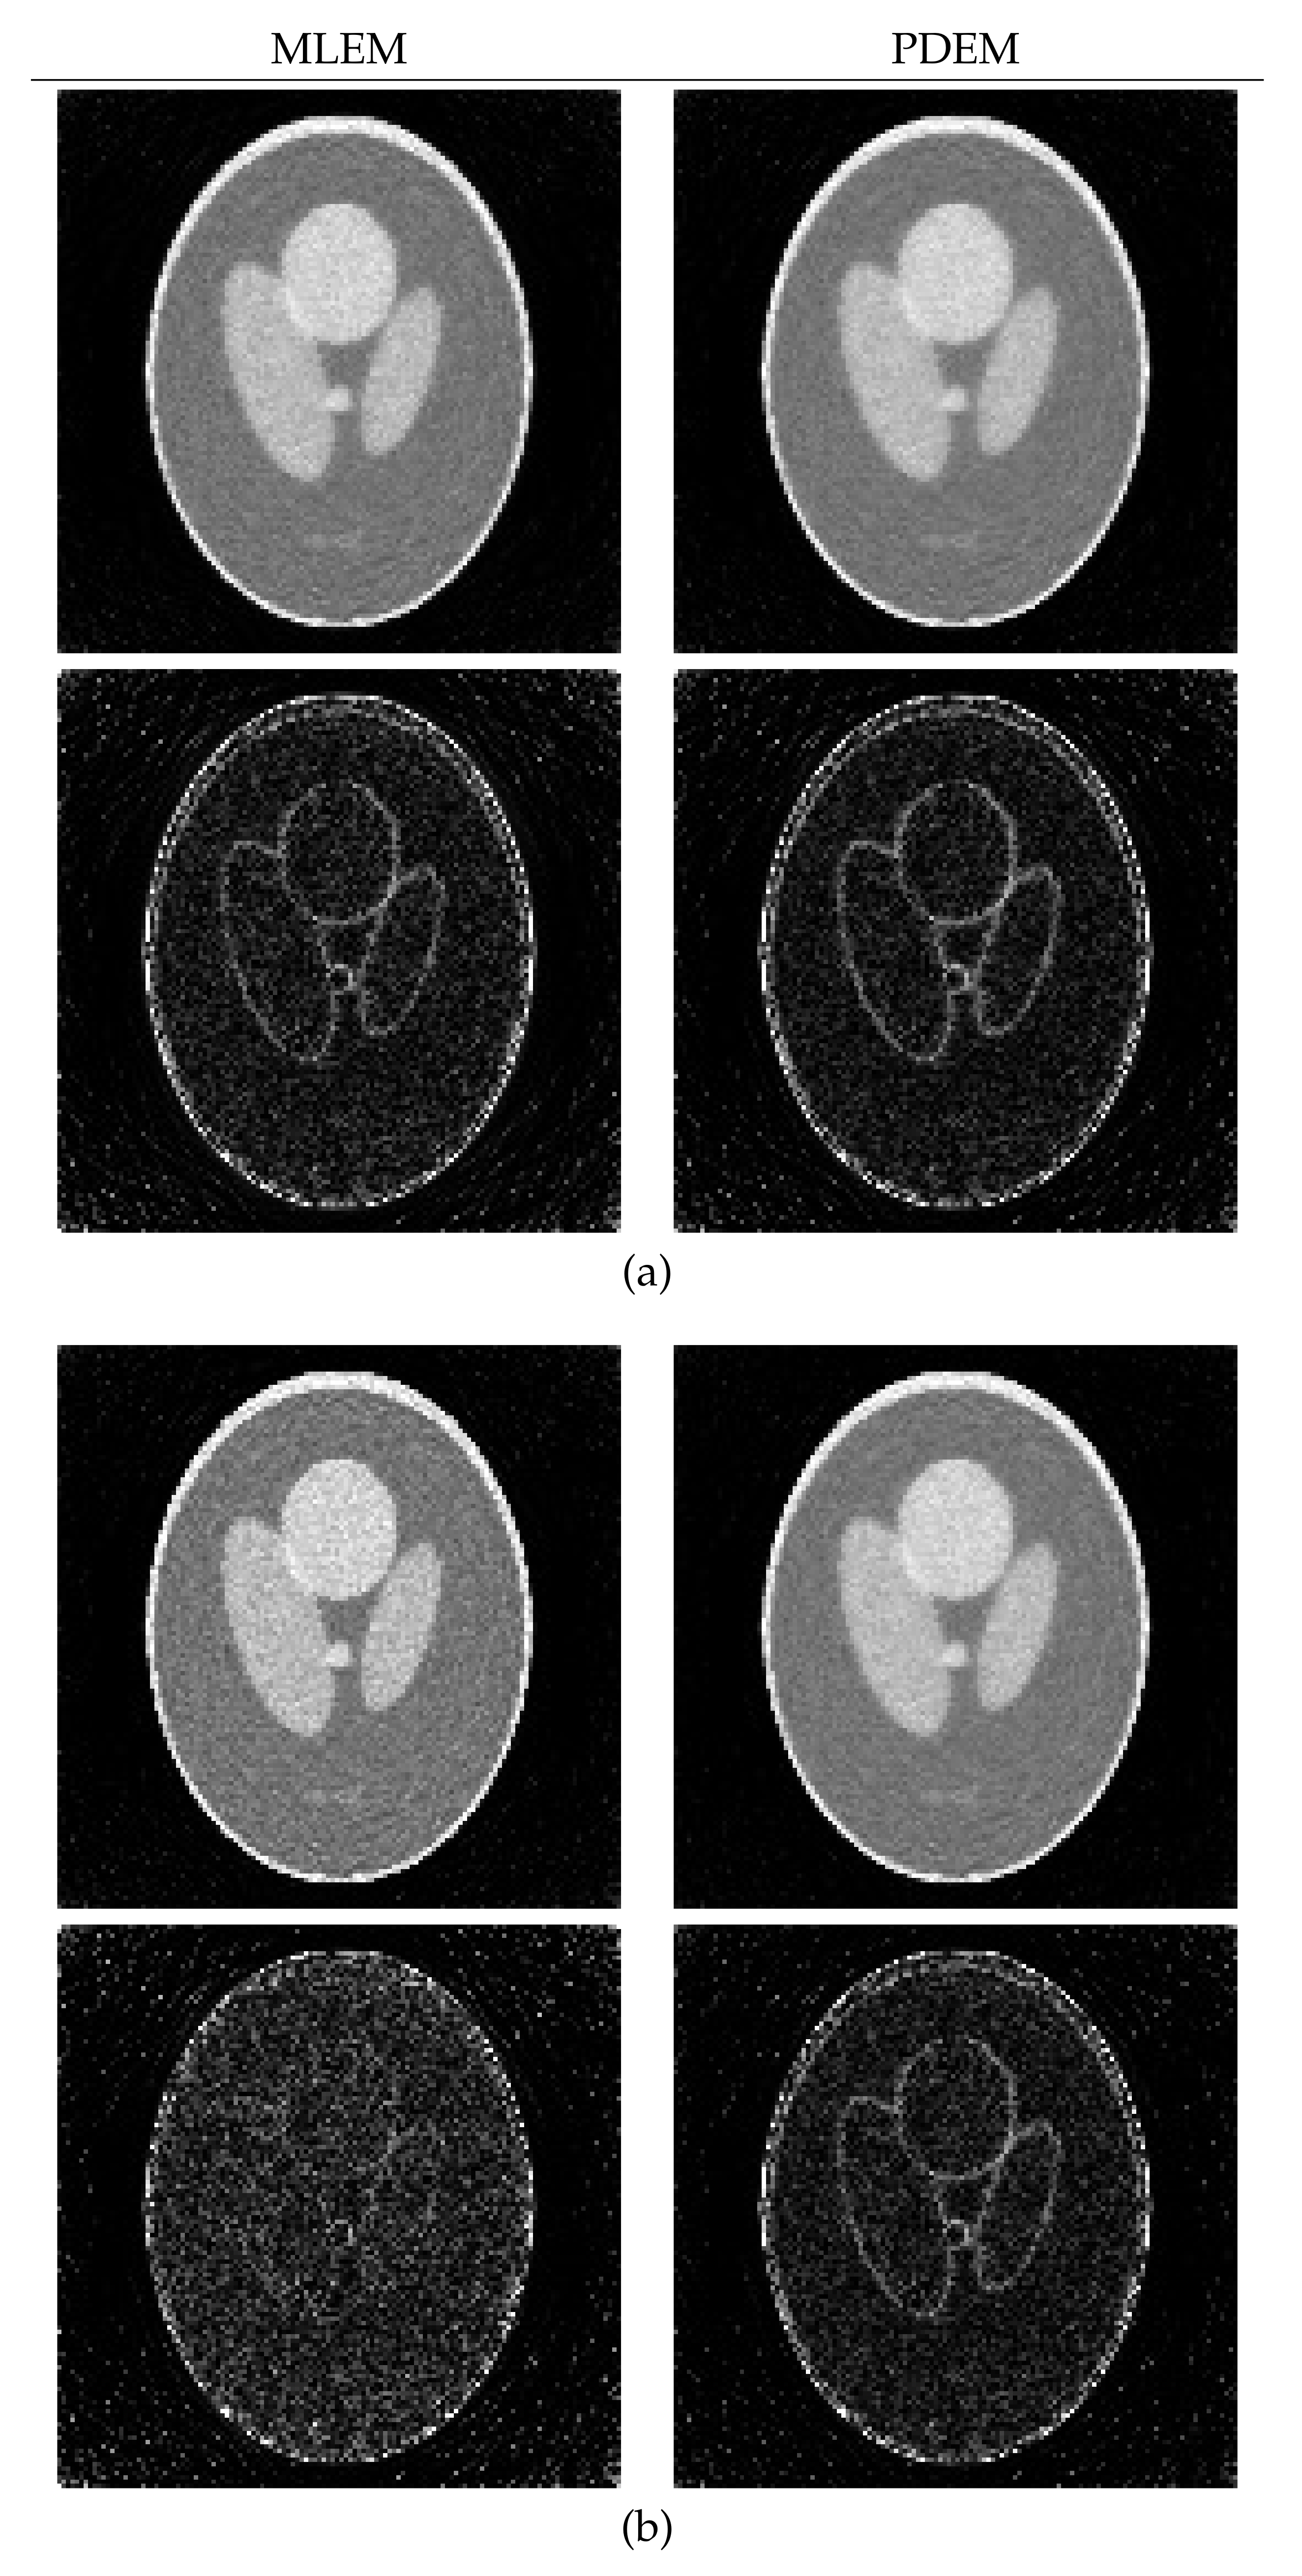

4.1. Reconstruction Using Numerical Phantom

| N | |||

|---|---|---|---|

| MLEM | PDEM with | ||

| 50 | 6.44 | 6.29 | (0.8, 1.2) |

| 100 | 6.65 | 5.85 | 0.5, 1.2) |

| 200 | 7.86 | 5.70 | (0.3, 1.2) |

| N | SSIM | ||

| 50 | 0.651 | 0.689 | (0.8, 1.2) |

| 100 | 0.581 | 0.726 | (0.5, 1.2) |

| 200 | 0.531 | 0.772 | (0.3, 1.2) |